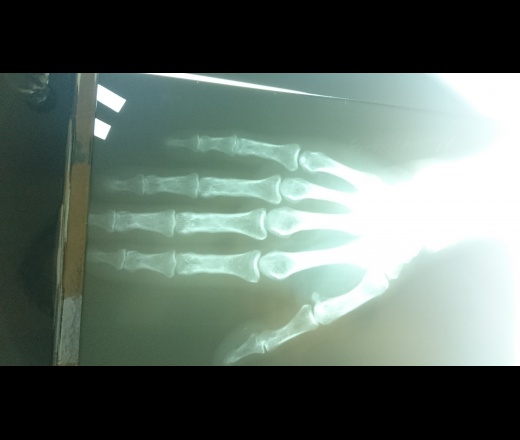

Хотелось бы услышать мнение коллег.Предпологаю,что просто доа2ст(остелпороз выраженный,кистовидные перестройки)Что еще можно добавить по поводу сгстояния костной структуры??

Кисты сомнительны. Больше, чем артроз I стд. не писала бы.